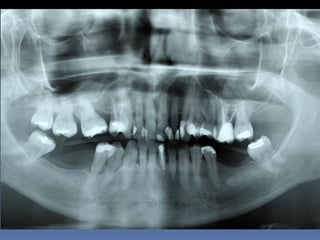

BOX 3

Kátia Maria Cavicchia

Idade – 43 anos

Sexo – Feminino

Raça – Caucasiana

ASA – II

Data- 29-04-2012

Diagnóstico: Desdentado parcial

bilateral posterior da mandíbula.

Plano de tratamento: Reabilitação bilateral posterior

mandibular com instalação de 6 implantes endo-

ósseos, para reabilitação protética fixa.

Zona 4.4, 4.5, 4.6   Zona 3.5, 3.6, 3.7